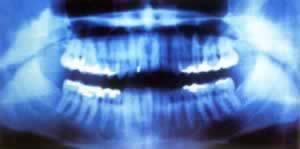

受这次偶然发现的激励,伦琴放下其他研究项目,集中精力调查X射线的特性。经研究他发现:X射线能使许多物质发光;X射线可以穿透不透光物质,他特别注意到,X射线能够透过他的肉体,只是为骨骼所阻,把手放在阴极射线管和荧光屏之间,能够在荧光屏上看到手骨的影子;X射线是直线,它与充电粒子束不同,不因磁场而折射……最后,伦琴以高超的实验技巧取得了9项关于X光重要性质的成果。由此可见,伦琴不是仅仅向荧光纸板方向看一眼就成为发现X光的巨人的,而是依靠敏锐的观察力、科学的预见力、准确的判断力、高超的实验力才成为杰出的科学家。1901年第一届诺贝尔物理学奖评选时,29封推荐信中就有17封集中推荐他。伦琴最终获得了第一次诺贝尔物理学奖金。